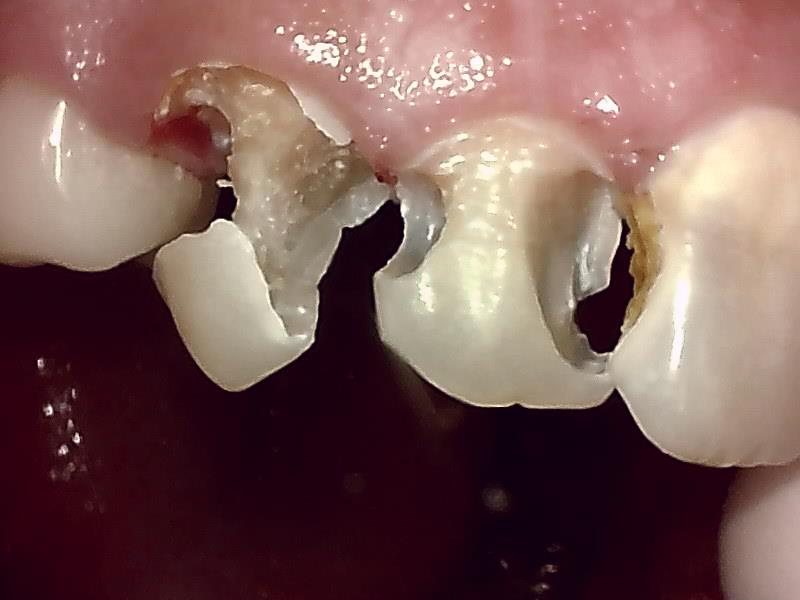

むし歯の治療例

治療例1

治療例2

治療例3

治療例4